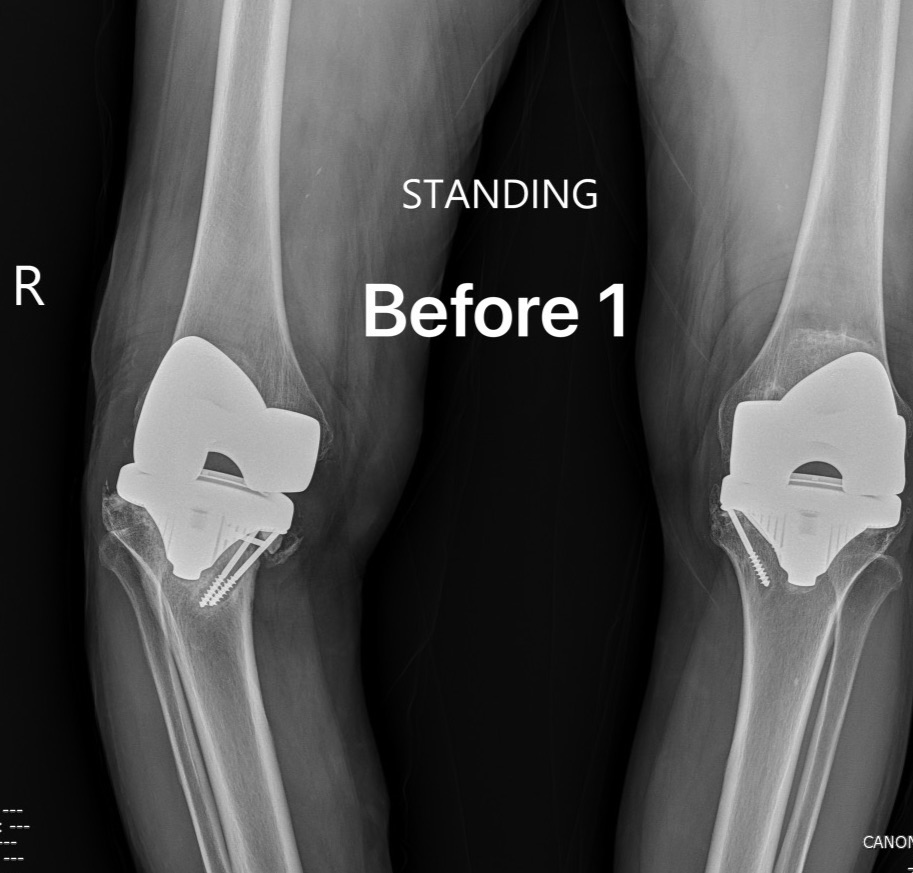

รวมภาพ X-ray Before/After Total Knee